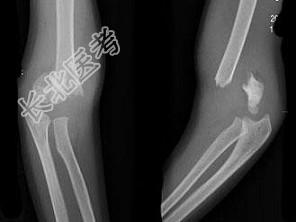

- 单项选择题男,8岁, 外伤后入院。结合图片,最可能的诊断是 ( )

A、Colles骨折

B、右肱骨髁上骨折

C、Smith骨折

D、孟氏骨折

E、青枝骨折